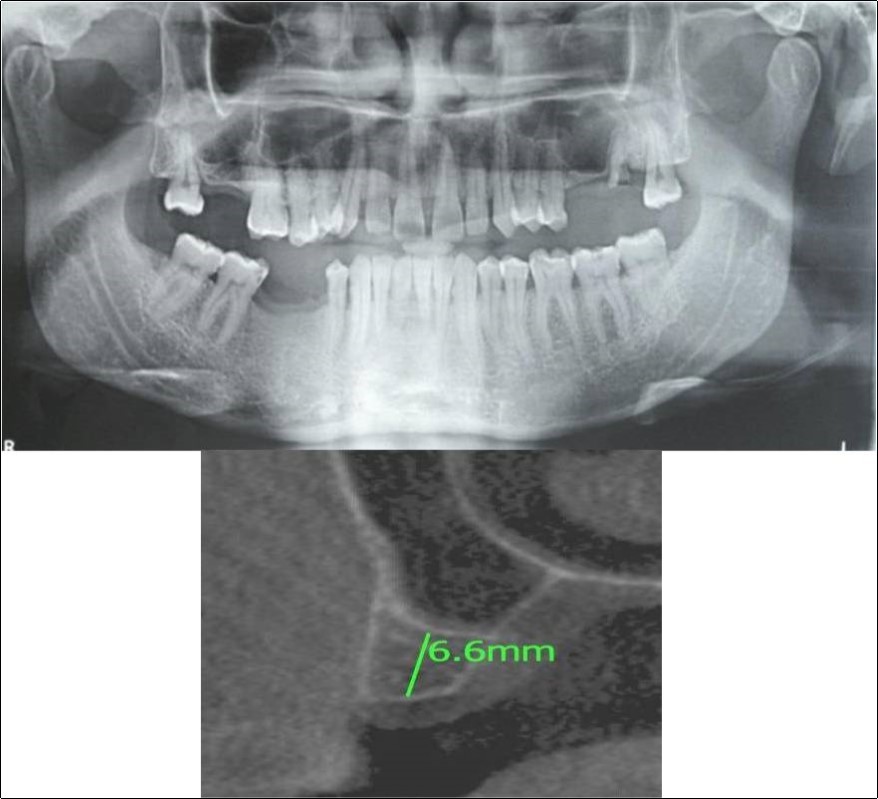

Clinical and Radiological Assessment:

1.Partially edentulous maxillary and mandibular arches with missing 17, 26, 45, 46;

2.Increased pneumatisation of right maxillary sinus;

3.Height of available bone- 6.6mm;

4.Transverse thickness of available bone (CBCT evaluation)- 11mm;

5.Inter-ridge space adequate to place implant (10mm).

Patient underwent the procedure of indirect sinus elevation using sinus osteotomes in relation to 17 region. Calcium phosphosilicate putty was dispensed as the graft material through the crestal osteotomy site to maintain the elevated sinus membrane followed by placement of a dental implant measuring 5 x 10mm under local anaesthesia and strict aseptic protocols .The implant was allowed to osseo-integrate for a period of six months during which the patient was followed-up periodically and was assessed for peri-implantitis, crestal bone loss and mobility. At the end of 6 months, a repeat CBCT scan was advised to evaluate the increase in bone height. (Figure 9a,b, pre-treatment; Figure 10a,b, post-treatment)

Figure 9.(a,b) Pre-treatment OPG and cross section of CBCT showing residual alveolar bone height for Case No.2